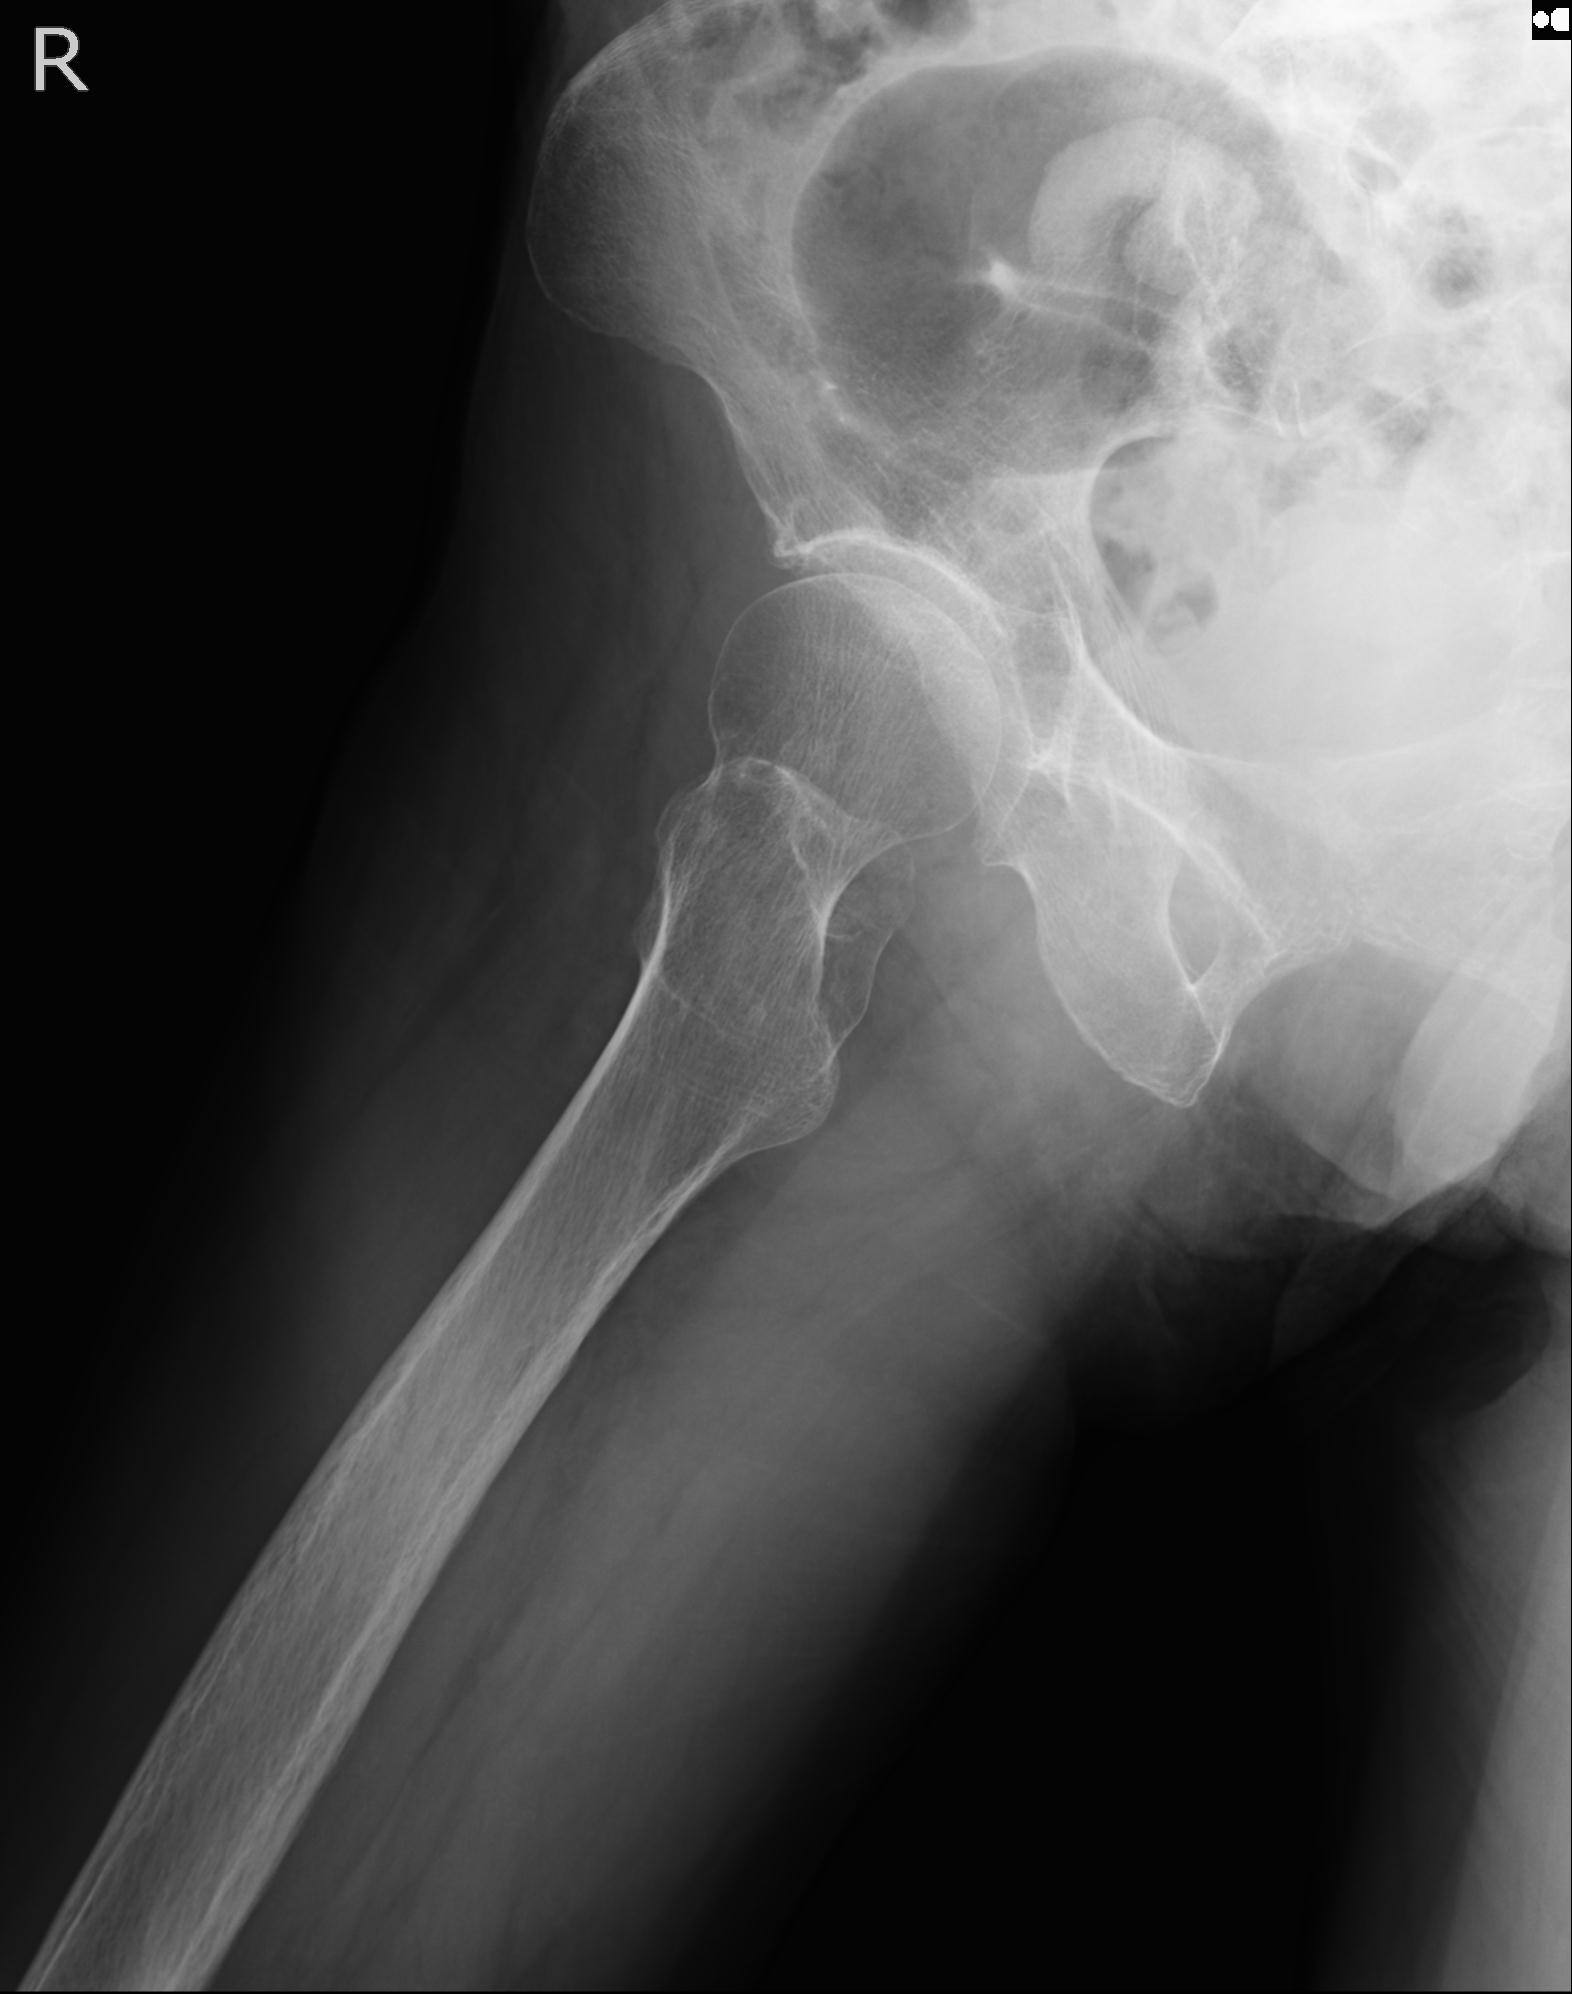

46666 1/28 両股正面+軸と 1/26 右手関節 2R 76歳女性 右転子部骨折